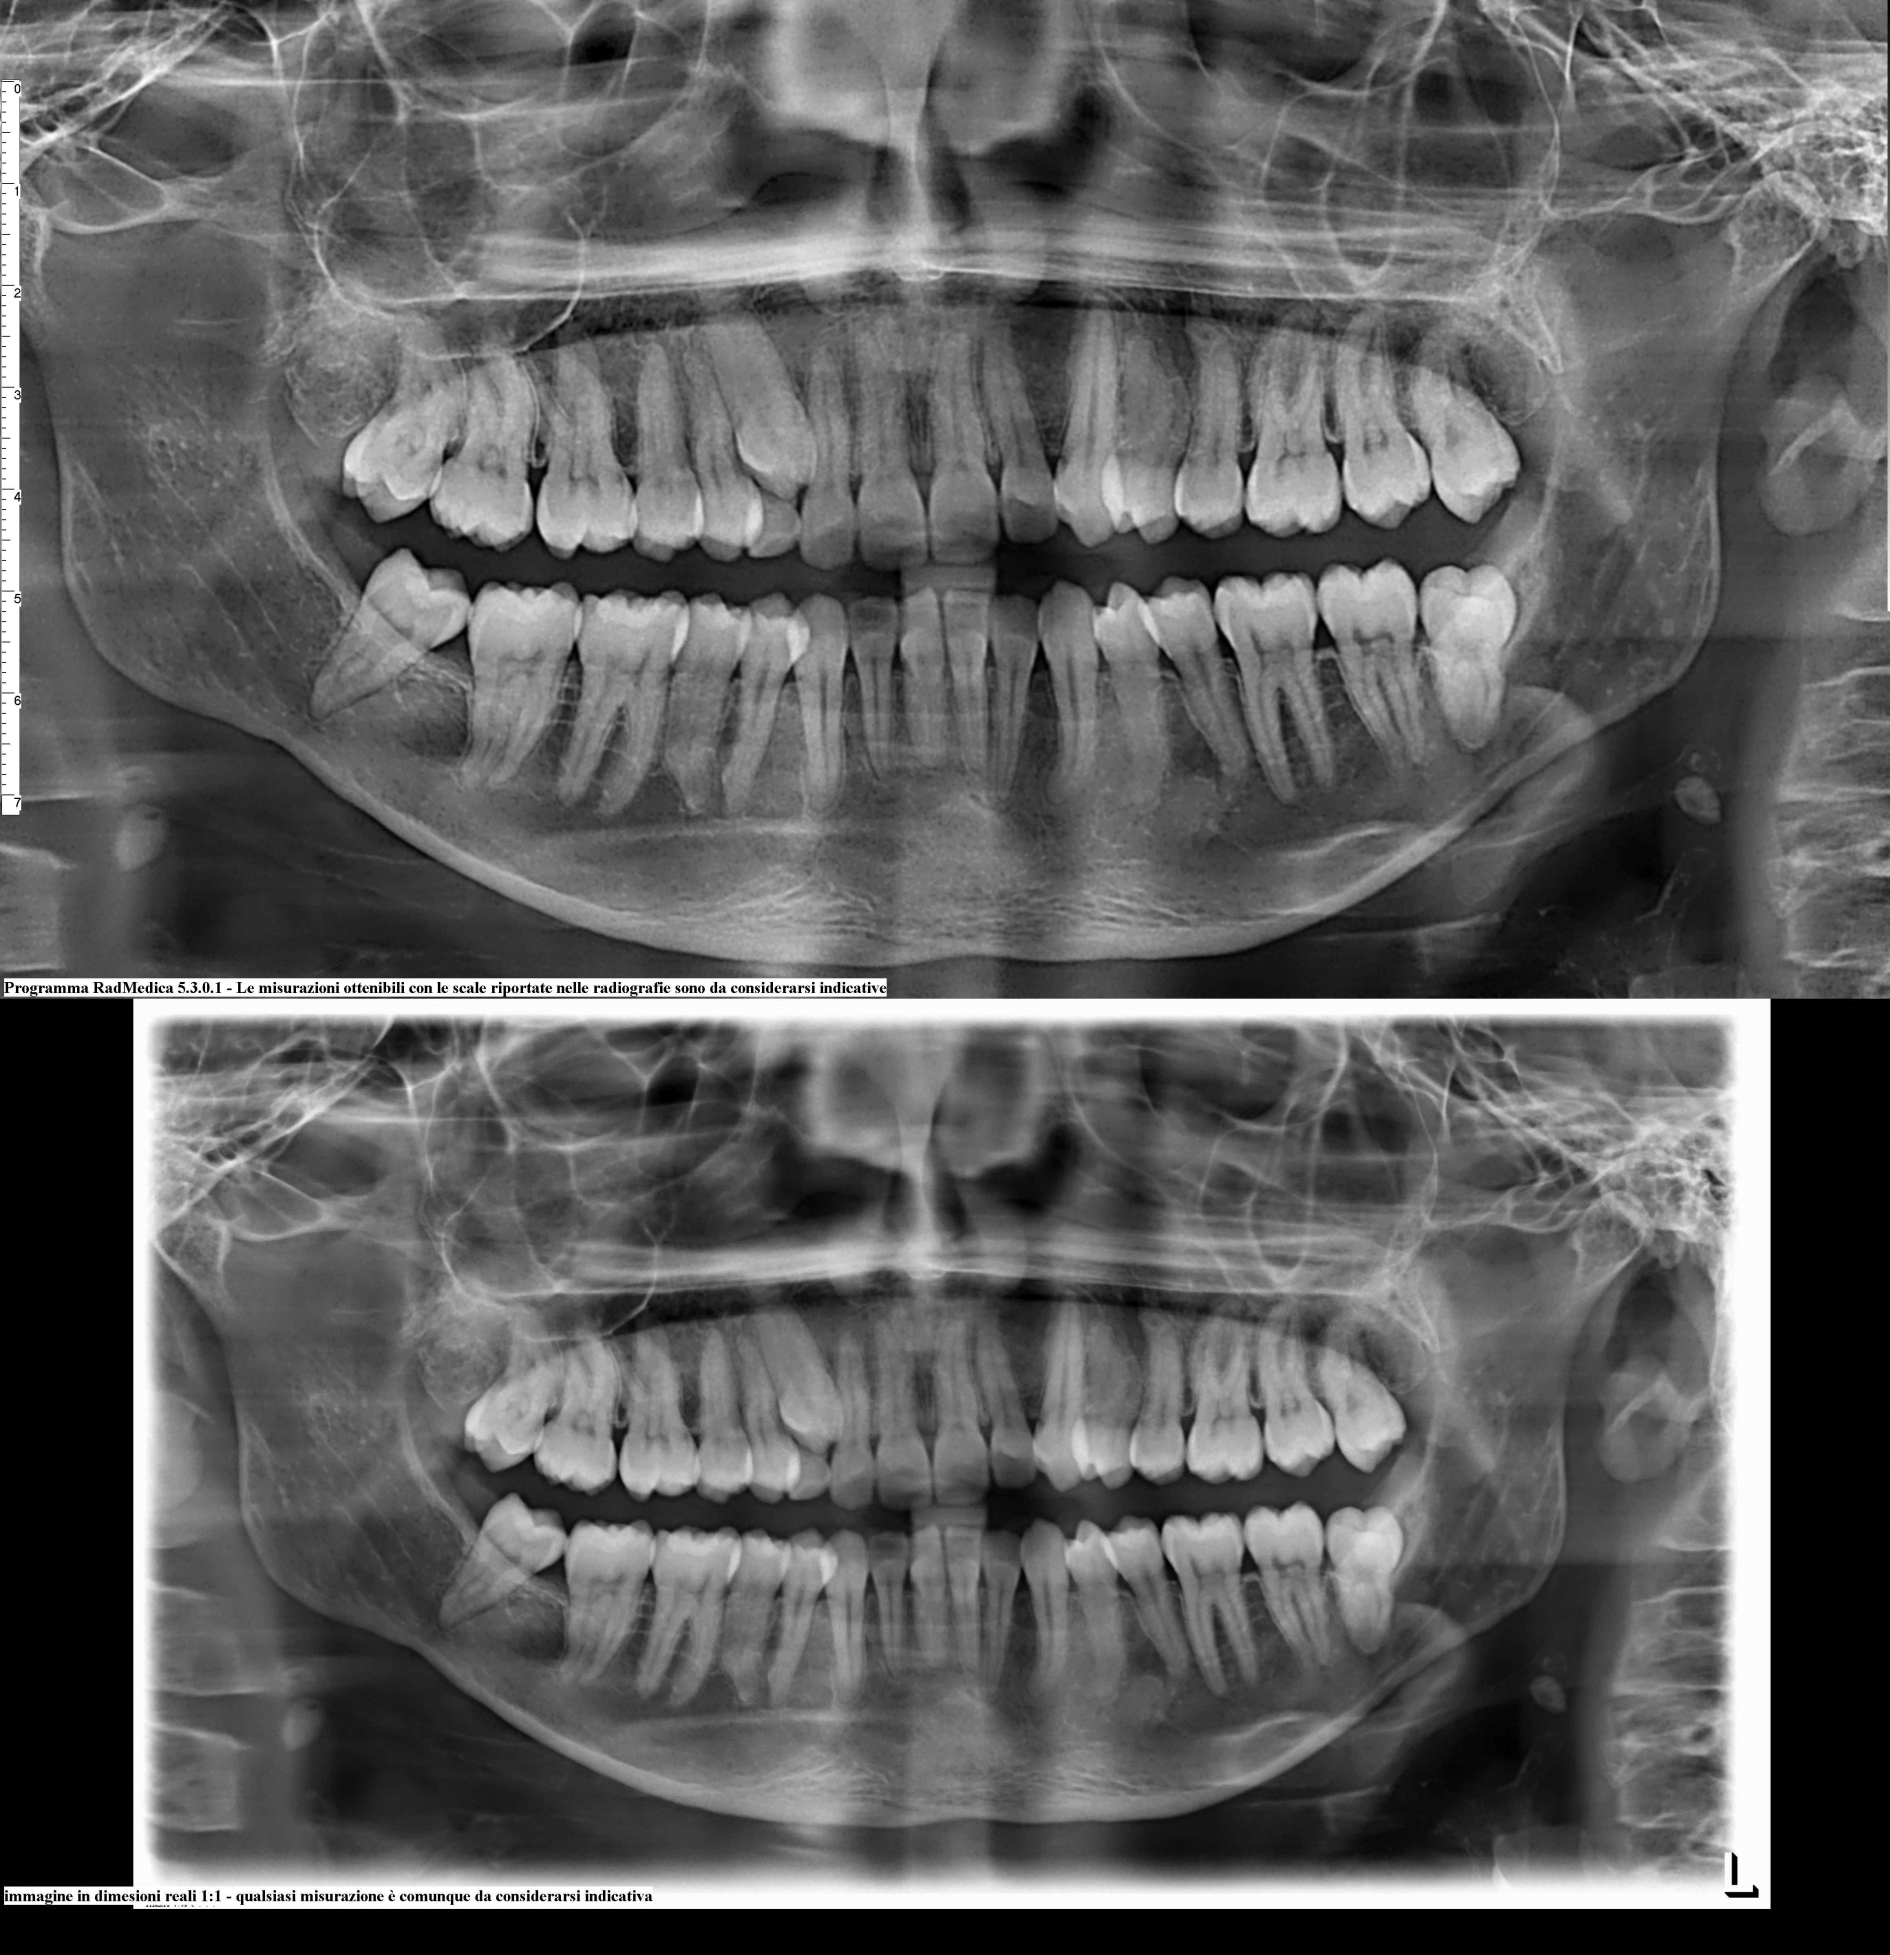

Buongiorno, la settimana scorsa ho scoperto, tramite una panoramica, di avere un'infezione ( nella zona mandibolare) vicino ad un perno installatomi anni fa subito dopo una devitalizzazione. La mia domanda è una sola: Non si può curare l infezione senza ricorrere all'estrazione del perno e installazione di un impianto?